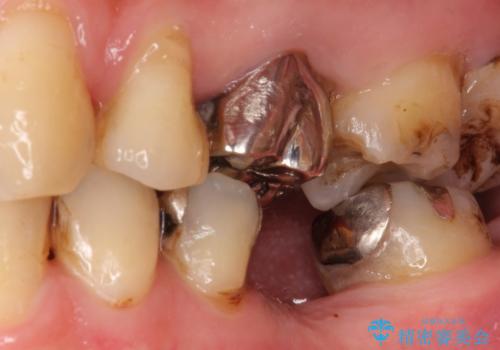

- 奥歯の補綴治療を主訴に来院されました。

今回はブリッジでの補綴を希望されたため、オールセラミッククラウンにより治療を行っております。

今回は両隣在歯に修復治療が行われており、外科治療を伴わないブリッジにて修復を希望され治療を行っております。